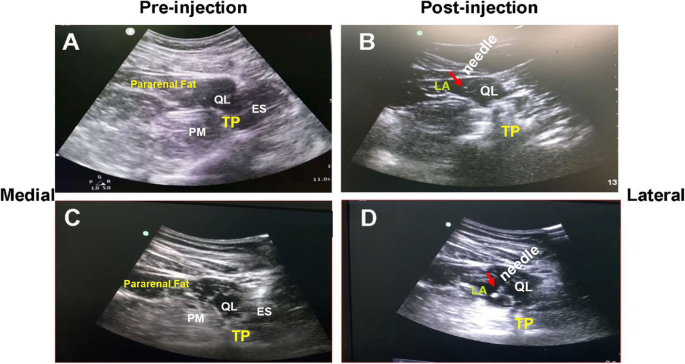

QLB-L technique (schematic illustration in Fig 1a and b): The patient was placed securely in the lateral decubitus position. A low-frequency curvilinear probe (SonoSite Edge, transducer C60x/5 2 MHz, Fujifilm Sonosite Inc., US) was attached above the iliac crest. Under the guidance of ultrasound, the 18 gauge 10-cm needle (Stimuplex® D, B. Braun Medical Inc., Germany) was applied to puncture from dorsal to ventral direction aiming at the anterolateral margin of the junction of QL and transversalis fascia, and 5 ml saline solution was injected to confirm the correct position by hydro-dissection phenomenon [13]. The block was completed with the 0.375% ropivacaine at a volume of 0.5 ml/kg thereafter. The range of sensory block was tested 30 min after the procedure. Patients whose block plane of abdominal wall between T10-L1 level 30 min after the block were the eligible candidates receiving truncal nerve block technique for postoperative analgesia.

Schematic illustration of the procedure of QLB-L (a: Pre-injection; b: Post-injection of local anesthetics) and QLB-TM (c: Pre-injection; d: Post-injection of local anesthetics). QL: Quadratus lumborum; PM: Psoas major muscle; ES:Erector spinae muscle; TP: Transverse process; LA: local anesthetics; Red arrow: tip of the stimuplex needle®

QLB-TM technique (Fig 1c and d): The patient was placed in the same position as the QLB-L technique. The ultrasound probe was vertically attached above the iliac crest. The transverse process of second lumbar vertebra (L2) and typical shamrock image were identified, and the needle was inserted from the edge of the probe and proceeded further into the fascia between the QLM and psoas major muscle. The local anesthetics were injected into the accurate interfascial plane between these two muscles.